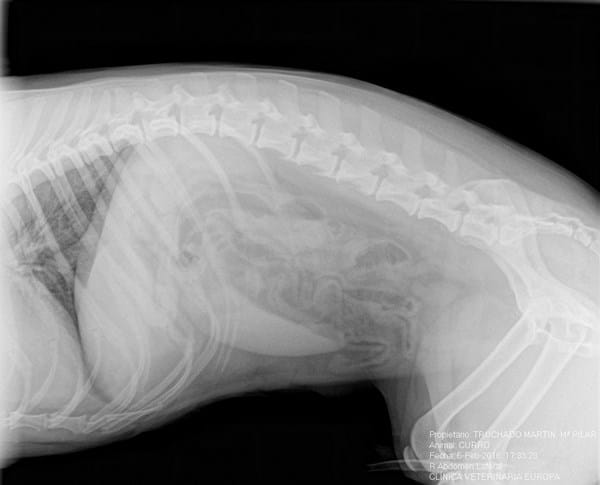

Tras la inspección y los rayo x la conclusión fue que se trataba de un problema lumbar o de columna, aparentemente una Hernia Discal... El perro el día anterior hizo vida normal, estuvo jugando por la noche en casa y se durmió en el sofá, se fue por su propio pie a su cama y a la mañana siguiente se levanto con los síntomas que fueron empeorando exponencialmente.

Adjunto Radiografía (realizada para ver si se trataba de un problema estomacal).